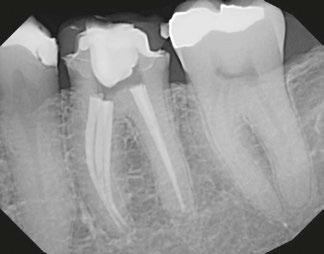

Figure 1 (left): Periapical radiograph taken at the time of tooth No. 11 crown delivery in 2018 with a periapical radiolucency extending distally toward implant No. 12. Figure 2 (right): Updated periapical radiograph taken in 2023 during a periodic oral exam showing clear delineation of a periapical radiolucency associated with tooth No. 11

Figure 3: Periapical radiographs taken during endodontic consultation in 2023. Periapical radiolucency originated from tooth No. 11 and extended toward implant No. 12. Calcification was appreciated in the coronal portion of the canal space on tooth No. 11

6A-6D: 6A. Preoperative periapical radiograph of

proper working

radiograph of tooth No. 11 confirmed proper master cone

periapical radiograph of tooth No. 11 verified length control and appropriate obturation

Figures

tooth No. 11. 6B. Periapical radiograph of tooth No. 11 confirmed

length. 6C. Periapical

fit. 6D. Postoperative

Figures 7A-7C: 7A. Immediate postoperative periapical radiograph. 7B.Periapical radiograph of tooth No. 11 at the 3-month reevaluation showing a reduction in size of the periapical radiolucency. 7C. Periapical radiograph of tooth No. 11 at the 6-month reevaluation showing a further reduction in the size of the periapical radiolucency.